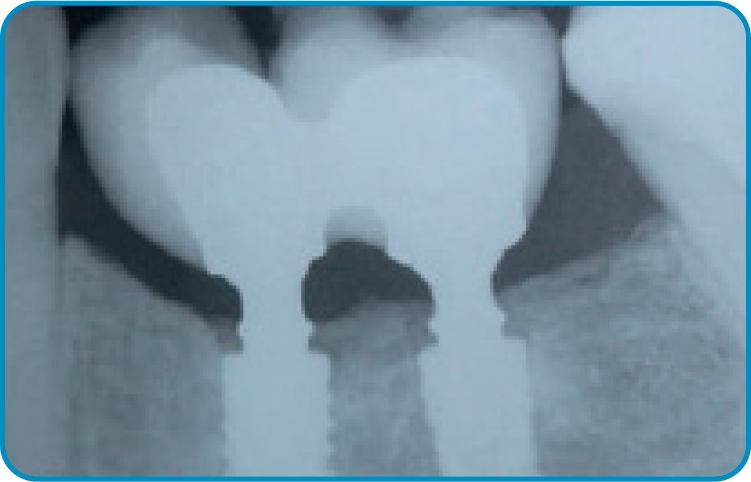

O caso clínico iniciou-se em 2015 com o objetivo de restaurar função e estética. Foram instalados dois implantes nas regiões dos dentes 35 e 36, seguidos pela osseointegração e condicionamento tecidual. As próteses finais foram confeccionadas sobre pilares Arcsys, com ajustes oclusais precisos. O acompanhamento clínico completa dez anos, com exames periódicos e manutenção regular. Observa-se excelente estabilidade óssea e saúde peri-implantar. O caso comprova que protocolos bem executados e componentes de qualidade garantem longevidade previsível.

4 | Acompanhamento radiográfico de dois anos em função.

5 | Imagem radiográfica evidenciando a estabilidade tecidual ao redor dos implantes após dez anos de função.